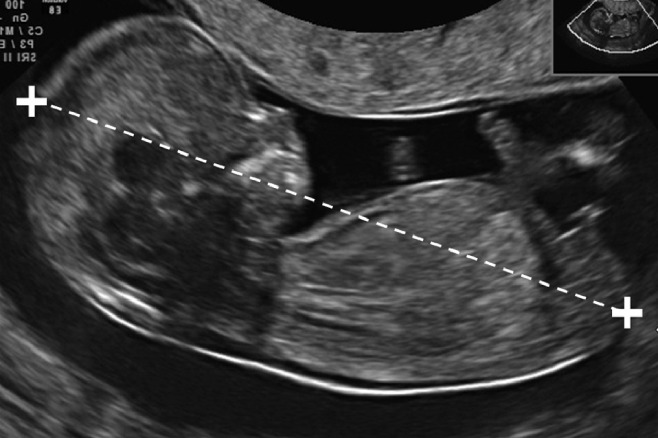

Image courtesy: https://obgyn.onlinelibrary.wiley.com/doi/10.1002/uog.12342